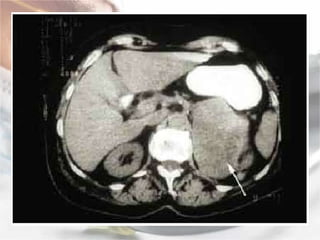

Localização:   A localização do feocromocitoma e feita com a utilização dos seguintes procedimentos radiológicos: tomografia computadorizada: com 85% a 95% de acuracia na localização de massas adrenais de ate 1 cm, não possibilitando a diferenciação entre feocromocitoma e metástases; ressonância nuclear magnética: que possui a capacidade de diferenciar feocromocitoma de adenoma ou carcinoma; mapeamento adrenal com I131 meta-iodobenzilguanidina (MIBG), de estrutura molecular semelhante a norepinefrina e que se concentra nas vesículas de estocagem de catecolaminas, possui 88% de sensibilidade, 100% de especificidade e 94% de acuracia na localização do feocromocitoma de ate 0,2 g de peso, de localização adrenal ou extra adrenal.